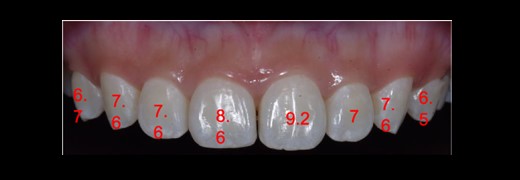

The length of the tooth crowns was clinically measured on the dental model (see Fig. 2), whereas the anatomical length was evaluated through CBCT images (see Figs 3 and 4). Based on the anatomical crown length, a smile design was created, and the patient was presented with a simulated smile before treatment (Figs 5 and 6). Upon approval of the simulated smile, a treatment plan was devised, establishing the future bone margin at 3-mm apical to the cementoenamel junction (CEJ) for each tooth, as indicated in Fig. 7.